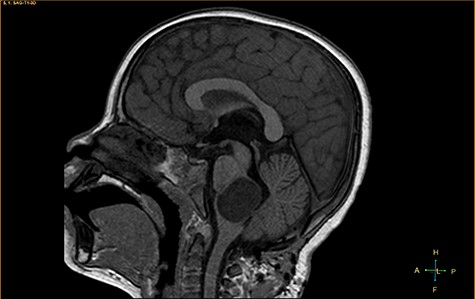

A 3-year-old male, who suffered from a sudden, tonic–clonic seizure, followed by a short period of unconsciousness, was instantly transported to Children’s Hospital 2. The patient’s medical history was normal. No neurological deficits were detected during the clinical assessment, and laboratory tests and electroencephalography were within acceptable ranges. The clinician performed a brain magnetic resonance imaging (MRI) scan, with contrast agent. No lesions were recognized in the supratentorial structures. A clear boundary cystic mass (27 × 25 × 26 mm3) was located in the medulla oblongata, without perilesional vasogenic edema. Hydrocephalus was not observed. The signal intensity of the mass was low on the sagittal T1-weighted image (Fig. 1) and high on the axial T2-weighted image (Fig. 2). On coronal fluid-attenuated inversion recovery imaging, the mass was isointense relative to the parenchyma, but the intensity was higher than that of cerebrospinal fluid (CSF, Fig. 3). On susceptibility-weighted imaging, no indicators of hemorrhage or ossification were observed within the mass. The mass was partially hyperintense on diffusion-weighted imaging (DWI) and slightly hypointense on the apparent diffusion coefficient (ADC) map. The mean ADC values of the parenchyma, mass and CSF were 0.71, 1.3 and 1.59 × 10−3 mm2/s, respectively (Fig. 4). On T1-weighted imaging, with contrast enhancement, the thin wall of the mass was very slightly enhanced, and we observed a tiny nodule inside the mass that was strongly enhanced (Fig. 5). With a provisional diagnosis of pilocytic astrocytoma, the patient underwent surgery to completely eradicate the tumor. Eventually, the histopathological result revealed a typical EC (Fig. 6). The postoperative period was uneventful, and the patient was discharged after 2 weeks.

Coronal fluid-attenuated inversion recovery image, showing an isointense mass relative to the surrounding parenchyma.